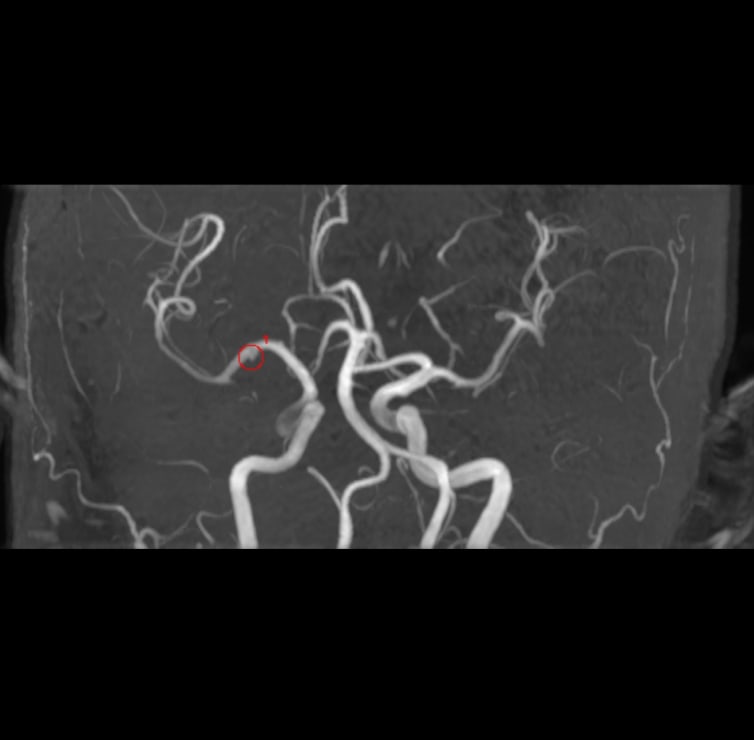

解析事例

中大脳動脈